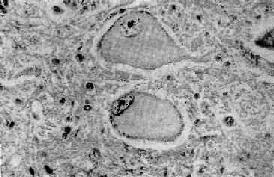

1.中央性Nissl小体溶解(central chromatolysis)这是一种可逆性变化,病因一旦去除,就可恢复正常,如病变继续发展,则可导致细胞的萎缩和死亡。常见的病因有病毒感染(如脊髓灰质炎病毒)、维生素B属缺乏、坏血病和神经元与轴突断离。病变表现为神经细胞肿胀,丧失典型的多极形状而变为圆形,胞核偏位,胞浆中央的Nissl小体崩溃成为细尘状颗粒,进而完全溶解消失,或仅在细胞周边部有少量残余。胞浆着色浅而呈苍白均质状(图16-1)。

图16-1 中央Nissl小体溶解

神经细胞肿胀,胞核偏位,Nissl小体仅见于细胞周边部